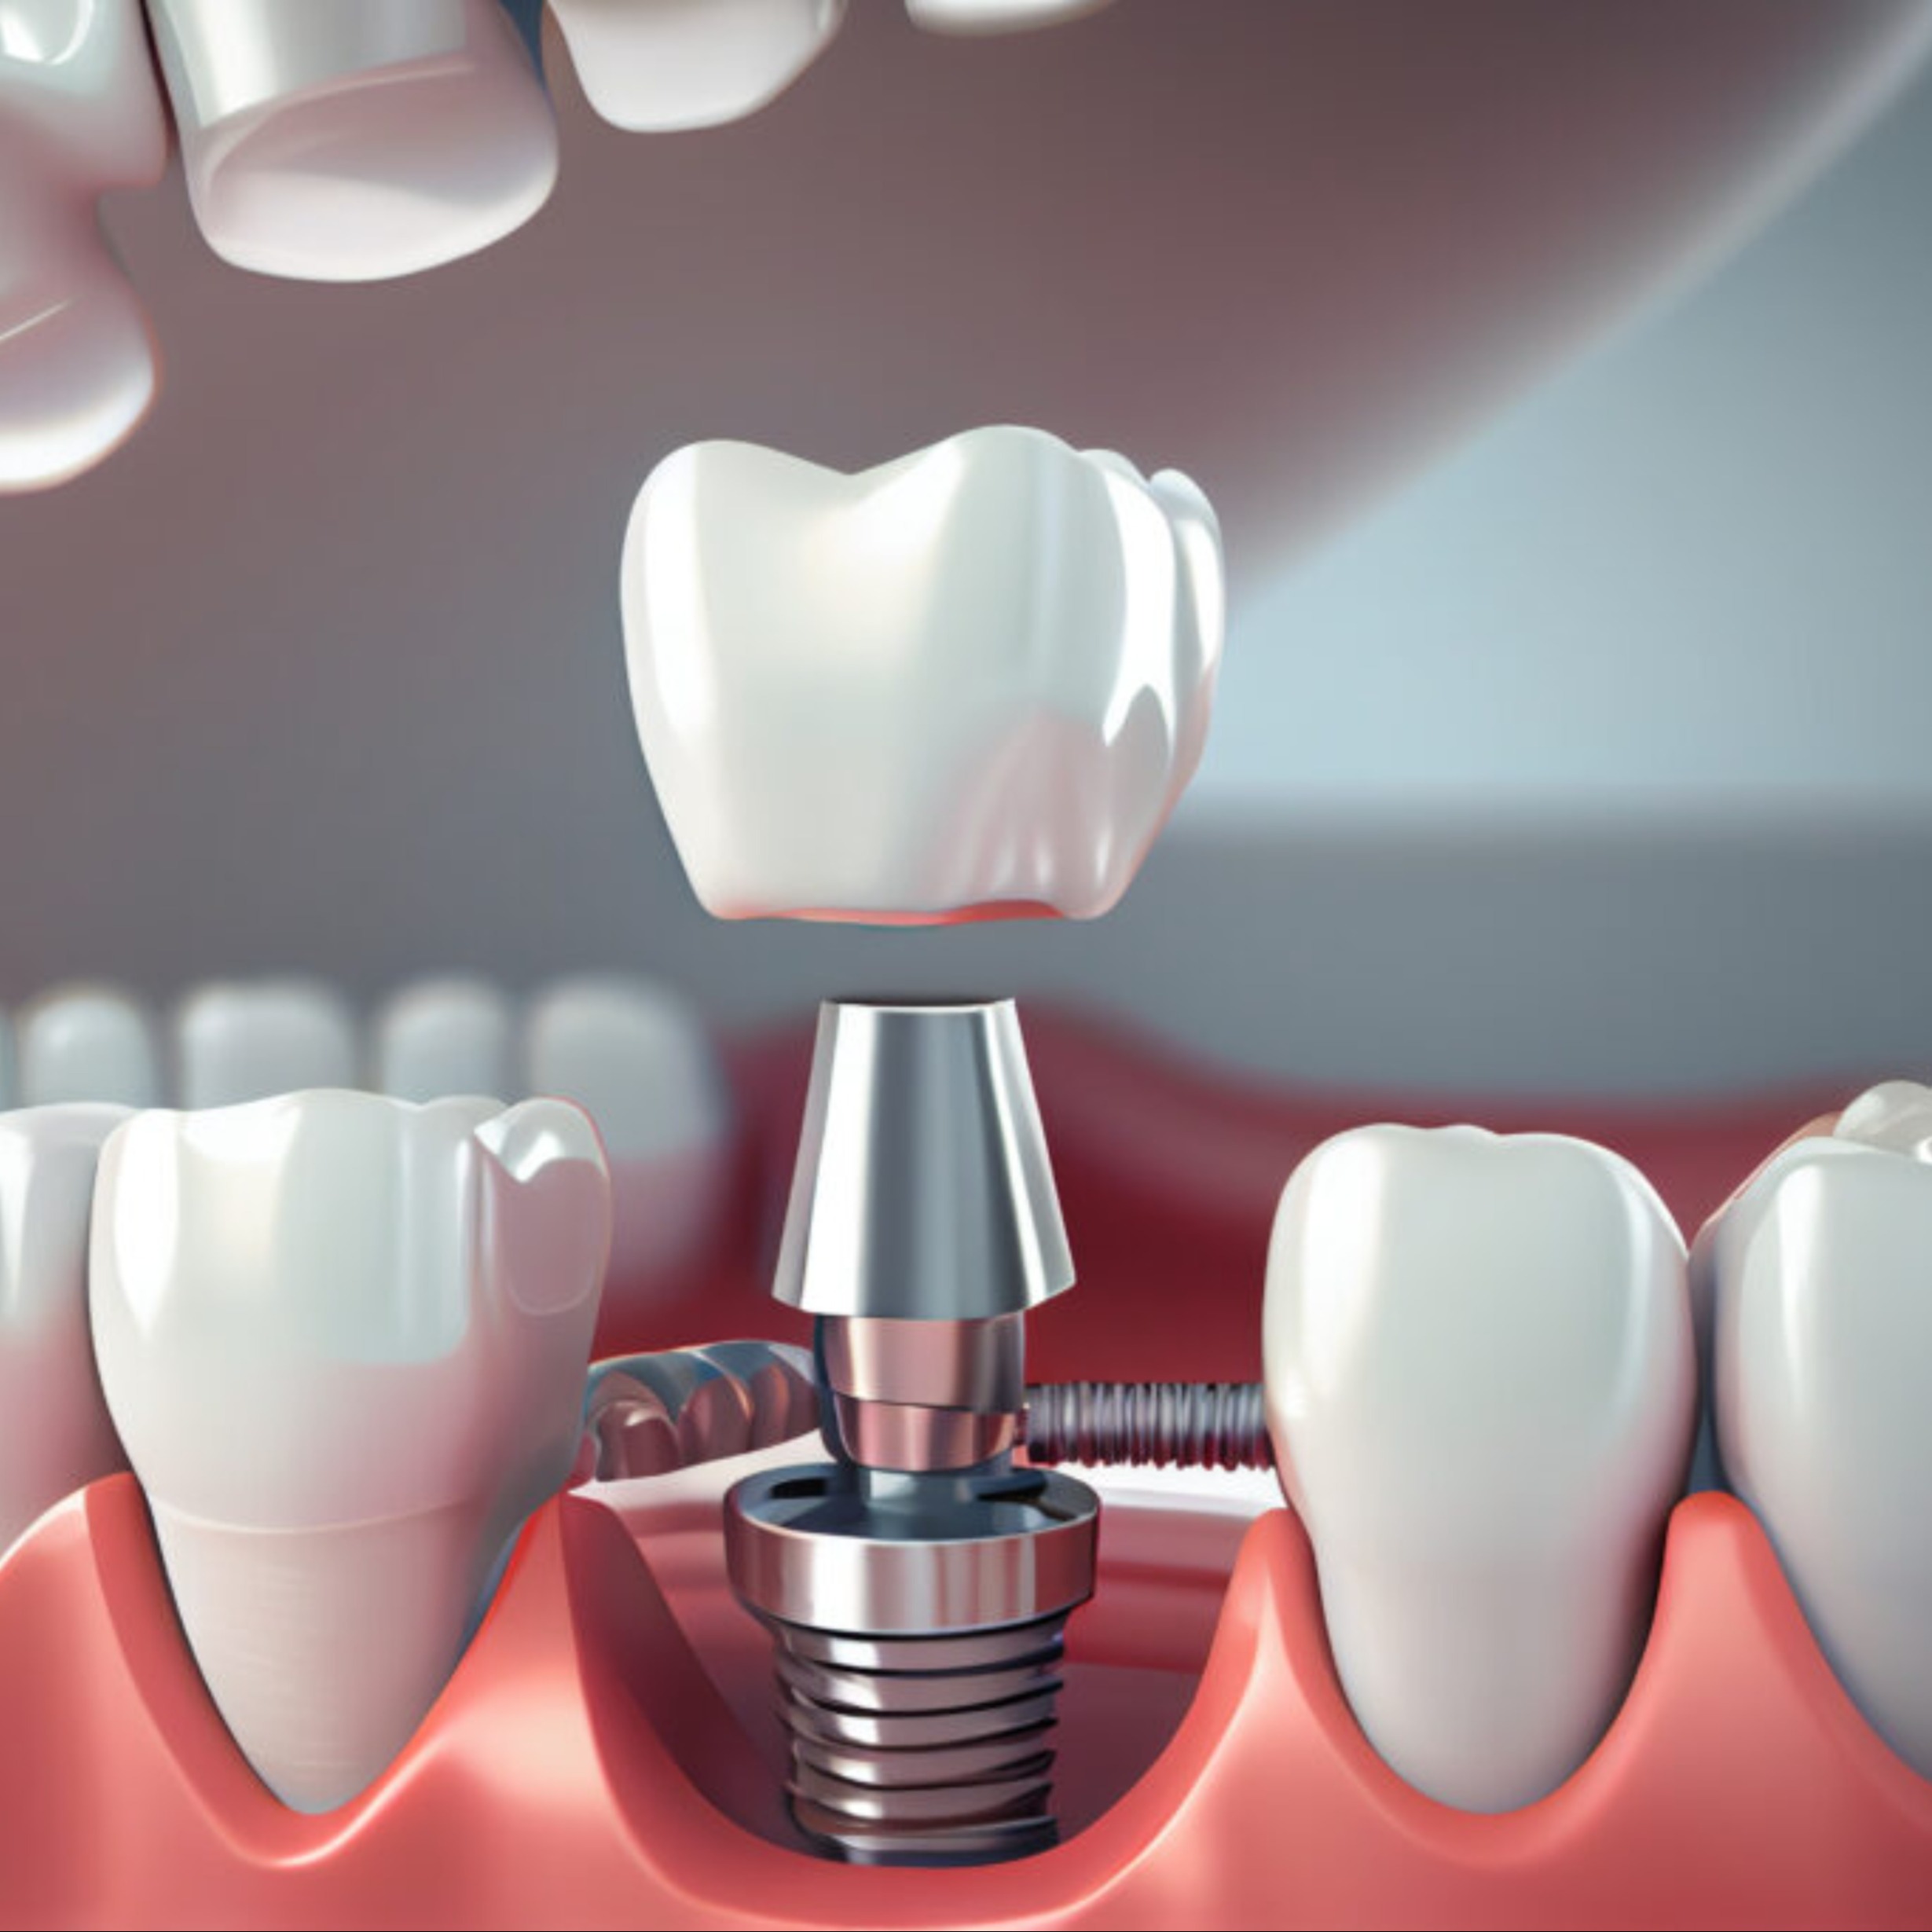

Trồng răng implant

Phương pháp nha khoa hiện đại giúp phục hình răng mất với các công nghệ và kỹ thuật tiên tiến